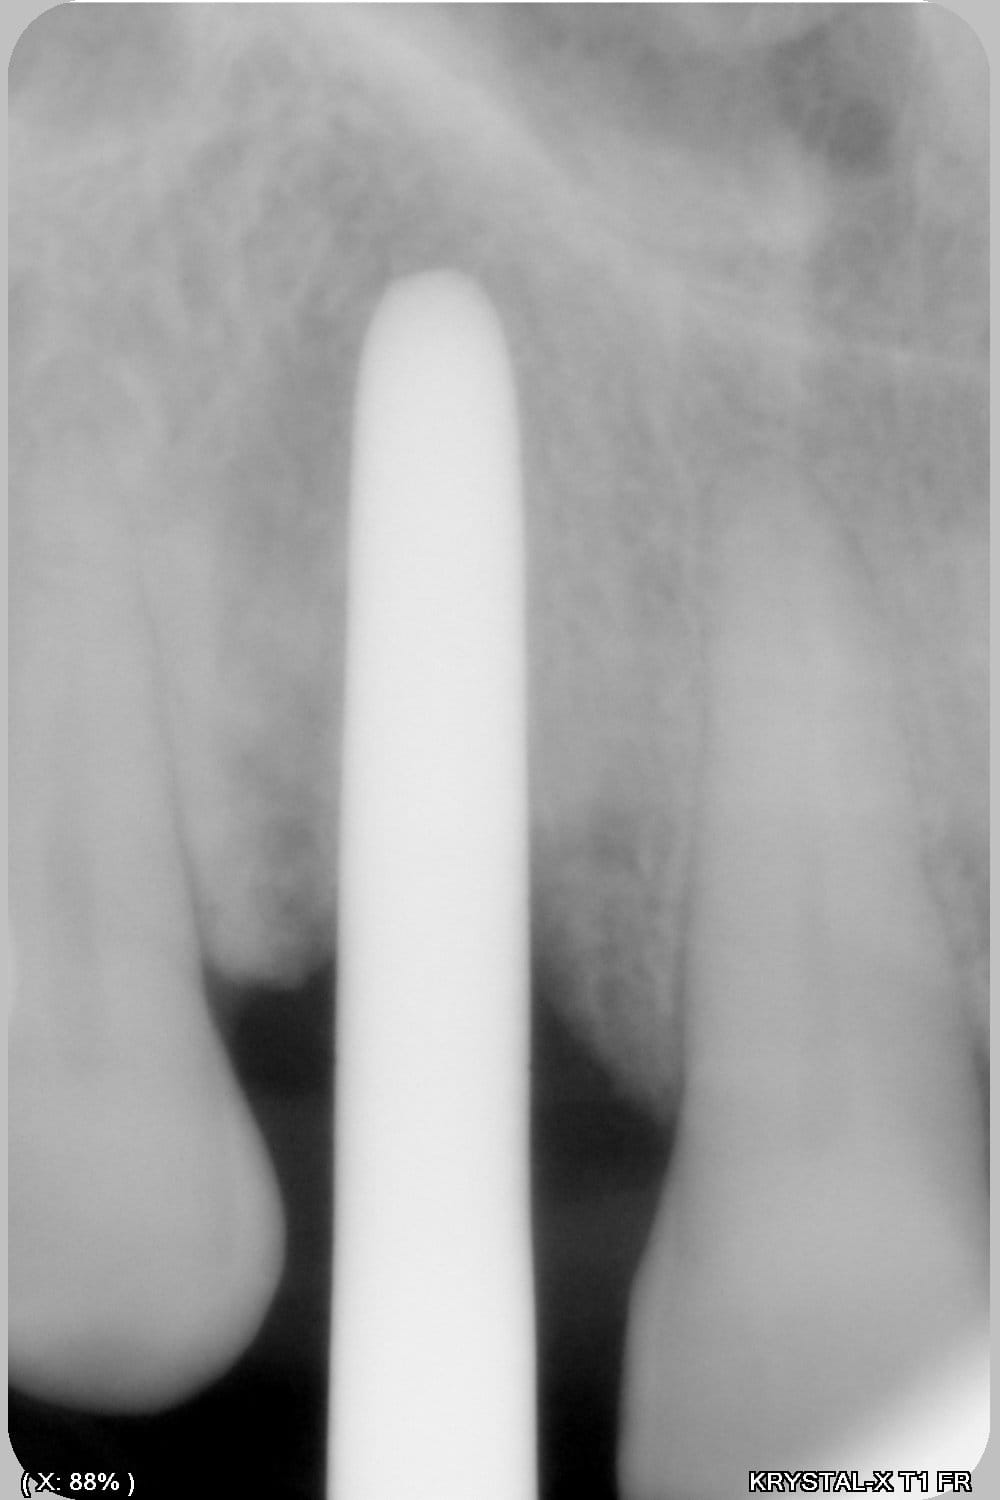

Thomas, tu as un plan pour guider dans un cas comme ça?

ou comment remplacer 12 avec soucis vestibulaire, par un implant, sans greffe, sans ROG, juste avec les mimines....?

Et bien pas de cone beam, pas de scanner,pas de panoramique...pour ne pas irradier l'os...et franchement je ne vois pas en quoi un guide me servirait dans un cas comme ça.